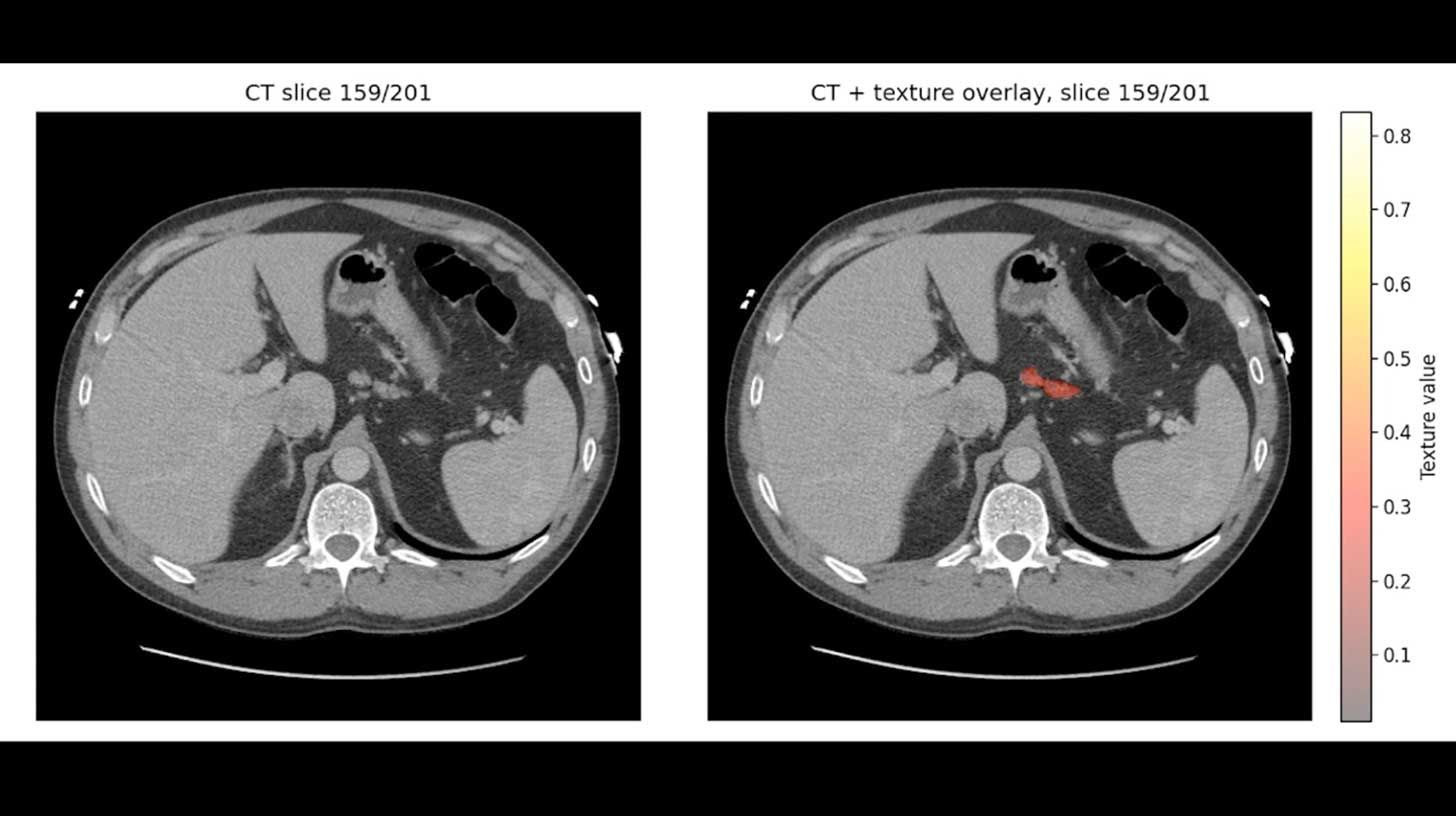

Mayo Clinic published new data on REDMOD, an AI system that detects invisible tissue patterns in standard CT scans. The model identified signs of pancreatic cancer up to three years before typical diagnosis and nearly doubled specialist accuracy.

Details:

REDMOD reviewed nearly 2,000 routine CT scans that specialists had originally read as normal before patients were later diagnosed.

The AI detected 73% of pancreatic cancer cases early.

Two years before diagnosis, REDMOD spotted roughly 3x as many early cancers as experienced radiologists.

The model analyzes hundreds of quantitative imaging, texture, and structural features that are usually invisible to human readers.

Why it matters:

Pancreatic cancer has a five-year survival rate below 15%, making earlier detection one of the most important levers for improving outcomes. Because REDMOD works on scans patients already receive, AI-based screening could become part of routine care instead of adding another diagnostic step.